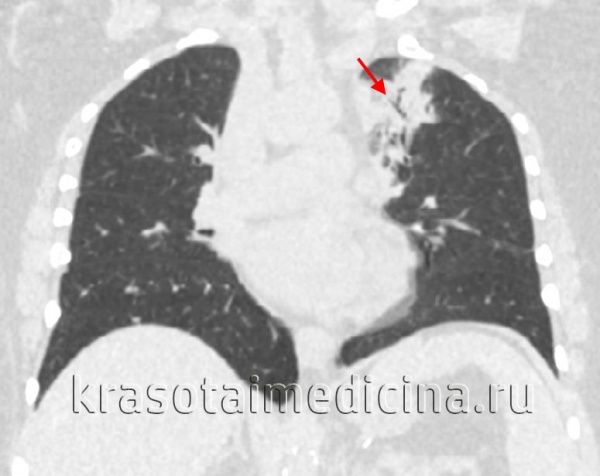

При подозрении на острую пневмонию назначается рентгенография легких в двух проекциях в динамике (на 7-10 день и 3-4 неделе). Рентгенологическим доказательством инфильтративных изменений при крупозной и крупноочаговой пневмонии является сегментарное или долевое гомогенное интенсивное затенение легочной ткани; при бронхопневмонии – неоднородное затенение части доли средней и малой интенсивности с захватом перибронхиальных и периваскулярных участков. В случае замедления рассасывания инфильтратов при острой пневмонии показана КТ легких.

КТ органов грудной клетки. Участок воспалительной инфильтрации (пневмония) в задних каудальных отделах нижней доли правого легкого